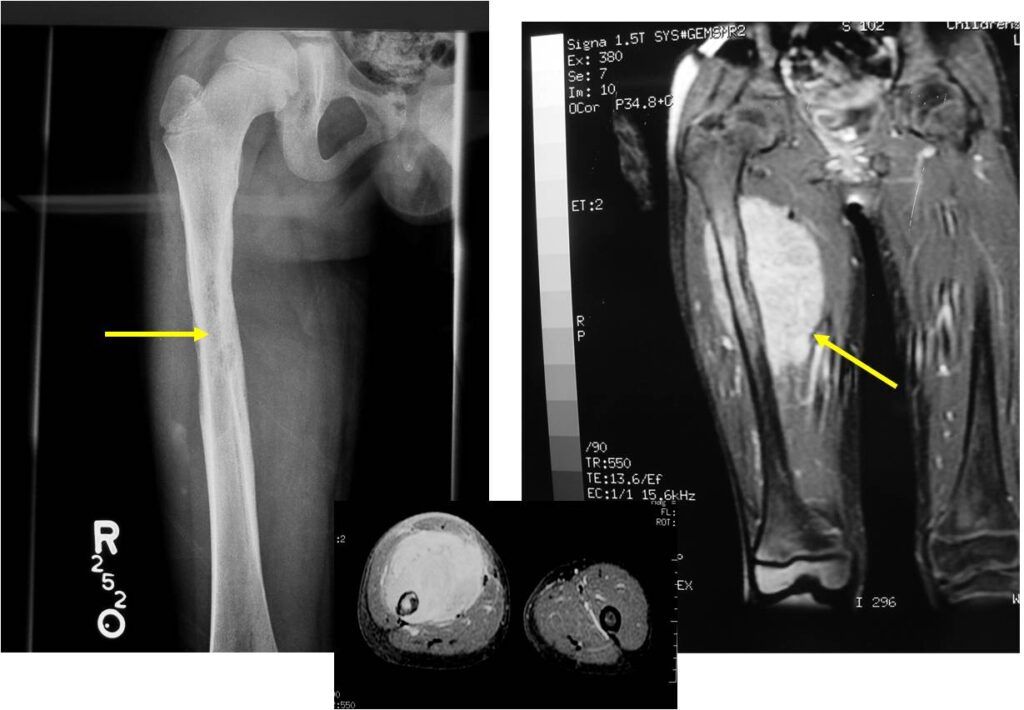

Radiographic Presentation

- Permeative or moth eaten bone destruction

- Ill defined and malignant appearing

- Bony changes are often subtle

- Soft Tissue Mass in 90% of of cases

- Periosteal Reaction in 50% of cases

- Onion Skin (colic pattern of irritation)

- Hair on End (rapid continuous lifting of periosteum)

- Reactive Bone Sclerosis is rare but occurs in 10% of cases

- No cartilage or bone production by tumor

- Pathologic fracture in 10-15%